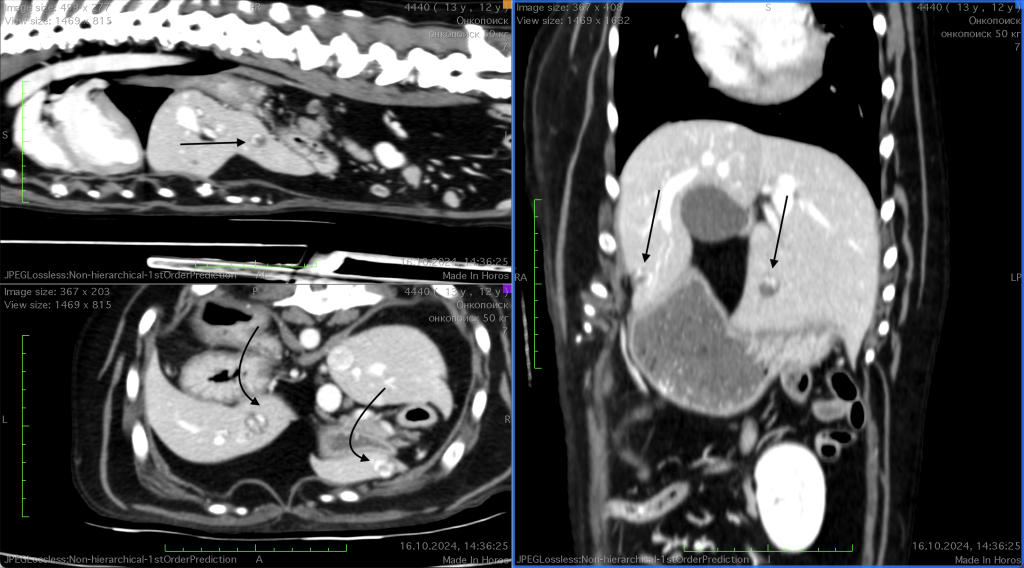

Актуальность. Гемангиосаркома (ГСА) селезенки у собак представляет собой злокачественное высокоагрессивное опухолевое заболевание с ранним метастазированием. Гемангиосаркома поражает преимущественно породы собак средних, крупных и гигантских размеров, а также их метисов. Стандартом лечения ГСА селезенки является спленэктомия с последующей адъювантной химиотерапией, однако прогноз остается осторожным, несмотря на проводимое лечение. Липосомальный доксорубицин (ЛД), обладающий способностью к селективному накоплению в опухолевой ткани и сниженной кардиотоксичностью, представляет интерес в лечении диссеминированных форм ГСА.Цель. Предоставить описание клинического случая применения ЛД у собаки с метастатической ГСА селезенки, оценить его эффективность и безопасность ЛД в сравнении со стандартным доксорубицином, включенным в комплексный противоопухолевый протокол VAC.